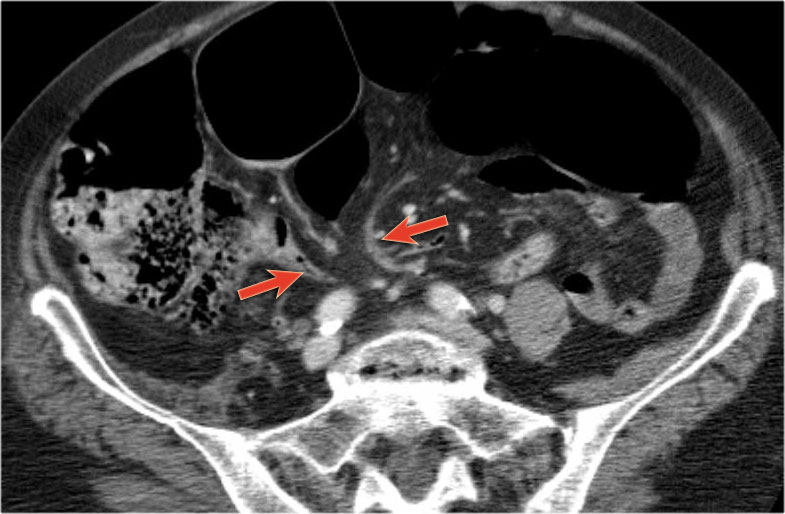

Đây là một bệnh nhân bị tắc ruột non.

Cuộn qua các hình ảnh.

Bạn có thể tìm thấy quai kín và nguyên nhân gây ra nó không?

Khi tiếp nhận bệnh nhân tại phòng cấp cứu với biểu hiện nghi ngờ tắc ruột non (SBO), điều quan trọng nhất chúng ta cần làm, ngoài việc chẩn đoán xác định, là xác định sự hiện diện hay vắng mặt của tình trạng thắt nghẹt.

CT là phương pháp chẩn đoán hình ảnh được lựa chọn trong đánh giá bệnh nhân nghi ngờ tắc ruột non.

Hình ảnh CT của tắc ruột non dạng quai kín phụ thuộc vào hai yếu tố:

- chiều dài đoạn ruột tạo thành quai kín

- hướng của quai ruột so với mặt phẳng tạo ảnh

Nếu quai kín ngắn và nằm trong mặt phẳng tạo ảnh, chúng ta sẽ thấy quai ruột hình chữ U hoặc chữ C.